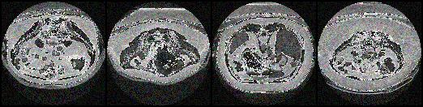

Segmentation is considered to be a very crucial task in medical image analysis. This task has been easier since deep learning models have taken over with its high performing behavior. However, deep learning models dependency on large data proves it to be an obstacle in medical image analysis because of insufficient data samples. Several data augmentation techniques have been used to mitigate this problem. We propose a new augmentation method by introducing adversarial learning attack techniques, specifically Fast Gradient Sign Method (FGSM). Furthermore, We have also introduced the concept of Inverse FGSM (InvFGSM), which works in the opposite manner of FGSM for the data augmentation. This two approaches worked together to improve the segmentation accuracy, as well as helped the model to gain robustness against adversarial attacks. The overall analysis of experiments indicates a novel use of adversarial machine learning along with robustness enhancement.